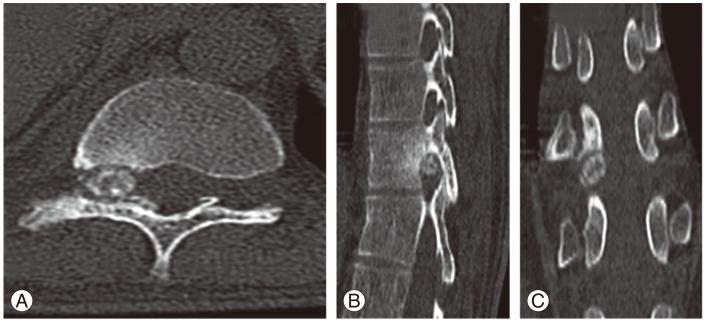

Osteoblastomas are bone forming lesions arising mainly from posterior elements of the vertebra. They are commonly encountered in the cervical and lumbar regions. We present a case of a thoracic osteoblastoma which is extra osseous and is not communicating with any part of the vertebra present intraforaminally. This is a rare presentation of an osteoblastoma. Imaging studies do not accurately diagnose the osteiod lesion. The size of the lesion and cortical erosion seen on the computed tomography scan help in differentiating the osteoid osteoma and osteoblastoma, but they are less sensitive and specific. Thus a histopathology is the investigation of choice to diagnose the osteoblastoma. Early and adequate removal of mass prevents malignant transformation, metastasis, and recurrence. In our case we excised the pars interarticularis unilaterally, removed the osteoid mass intact, and performed unilateral instrumented fusion. There was no recurrence and solid fusion was seen at 3 years follow up.

骨母细胞瘤是主要起源于椎体后部结构的成骨性病变。它们常见于颈椎和腰椎区域。我们报告一例胸段骨母细胞瘤病例,该肿瘤位于骨外,与椎间孔内的椎体任何部分均无相通。这是骨母细胞瘤的一种罕见表现。影像学检查不能准确诊断骨样病变。计算机断层扫描上所见病变大小和皮质侵蚀有助于鉴别骨样骨瘤和骨母细胞瘤,但它们的敏感性和特异性较低。因此,组织病理学检查是诊断骨母细胞瘤的首选检查方法。早期充分切除肿块可防止恶性转化、转移和复发。在我们的病例中,我们单侧切除关节突,完整切除骨样肿块,并进行单侧器械辅助融合。随访3年未见复发,且融合牢固。